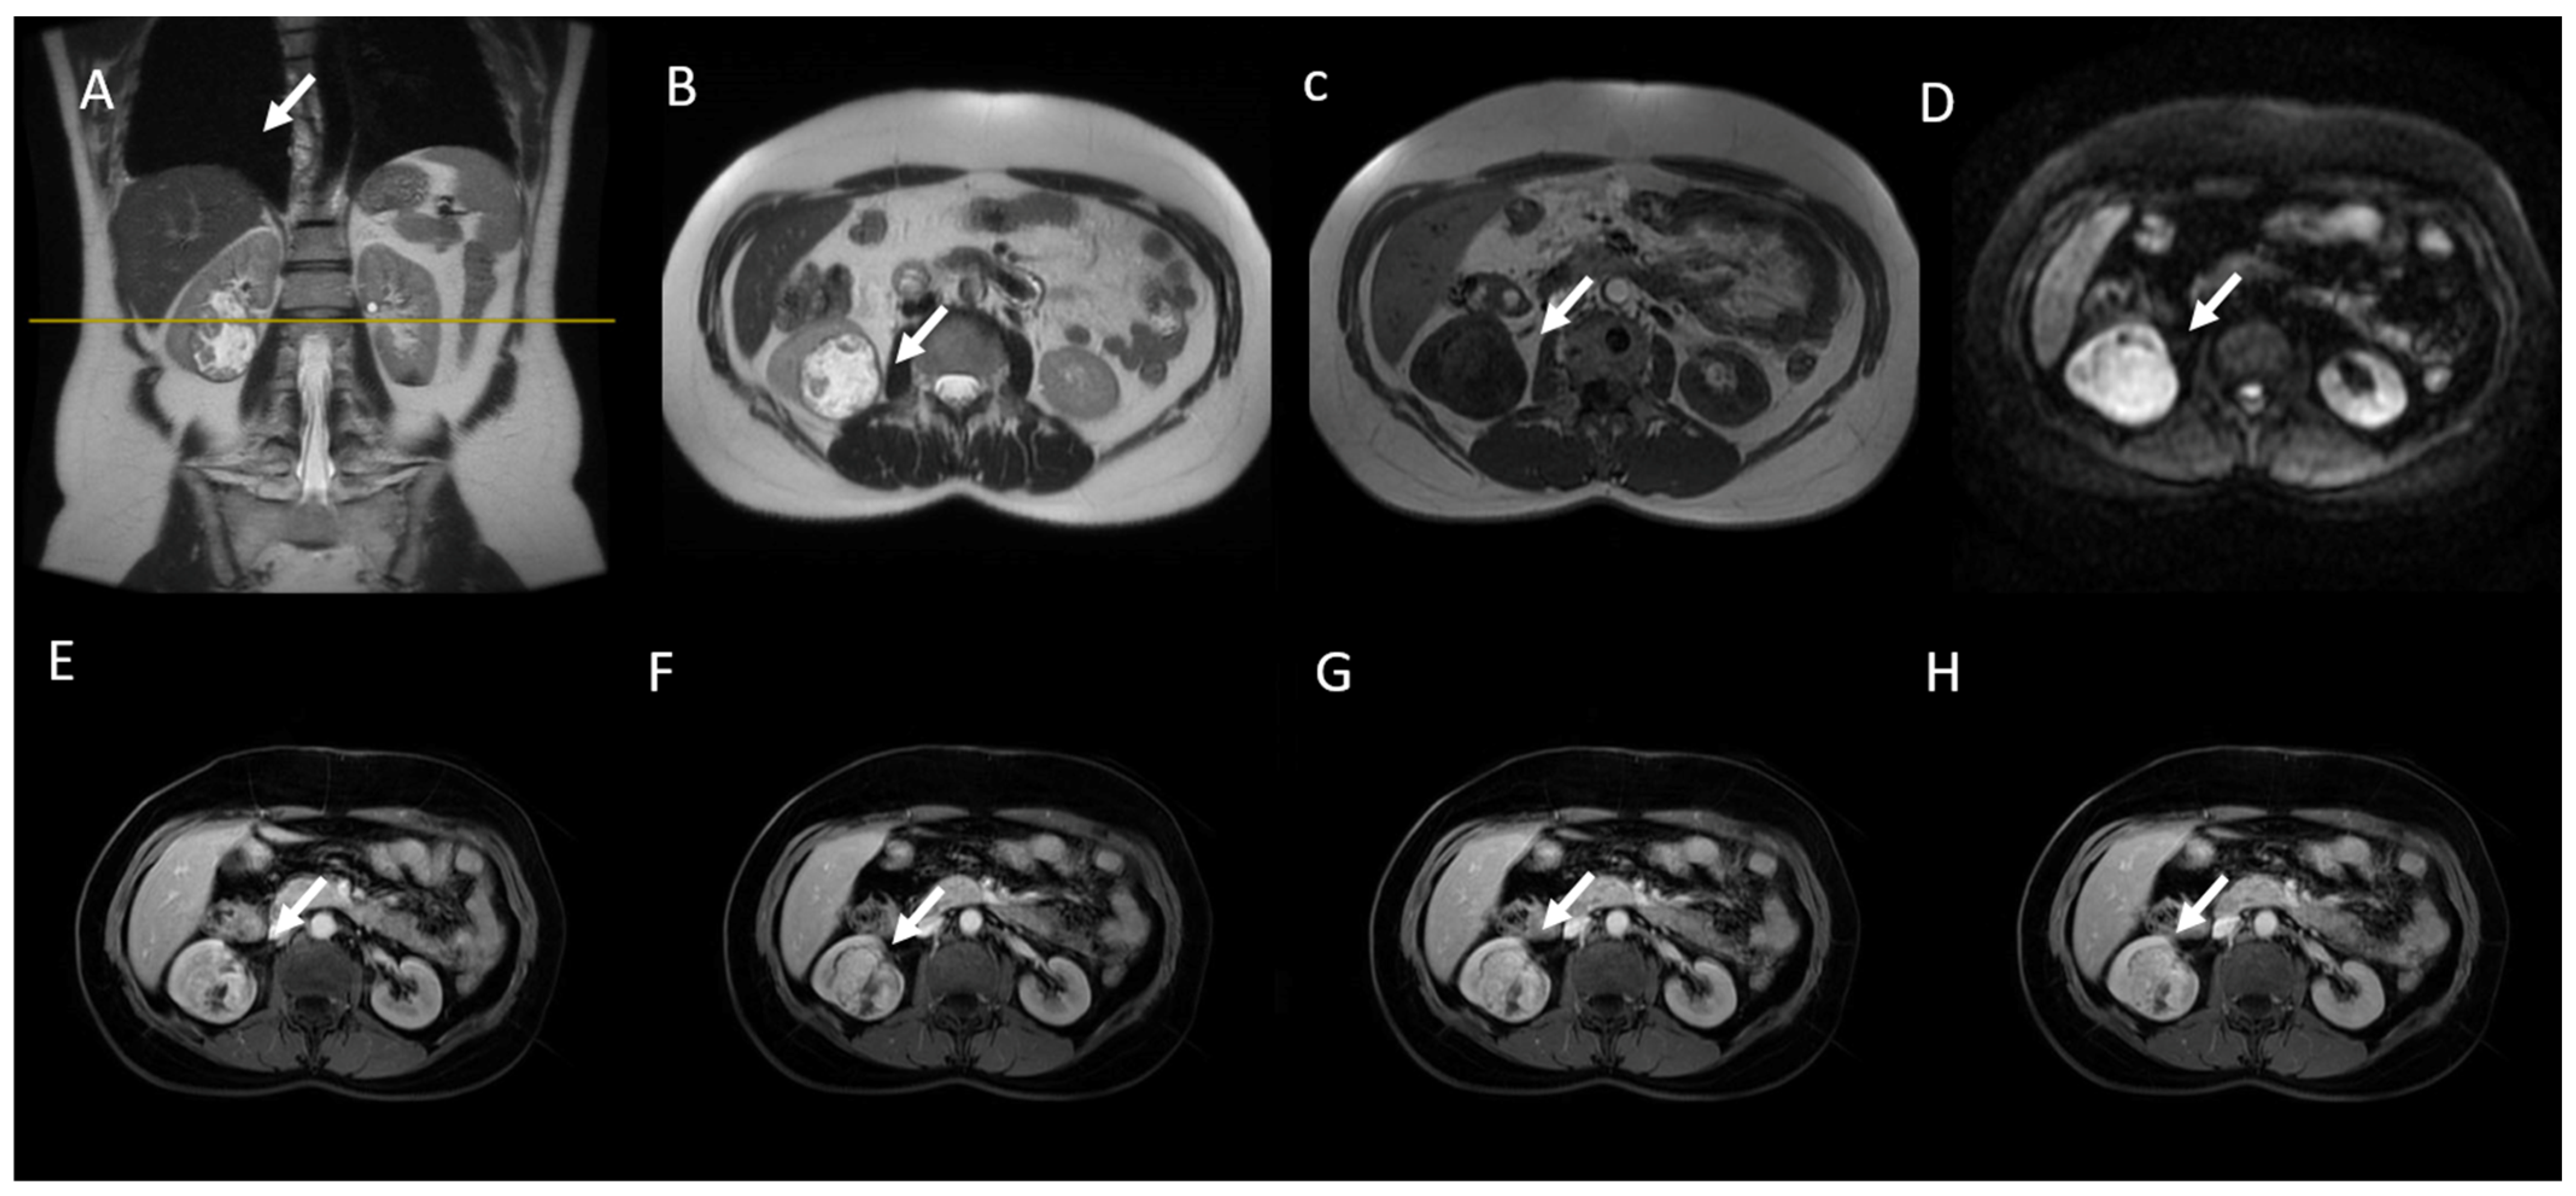

- (d) Class III: indeterminate cystic mass, which includes cystic masses characterized by one or more thickened (≥4 mm) or enhancing and irregular (≤3 mm and with convex marginal protrusions) walls or septa [91]. Bosniak III masses (Figure 4) are “potentially” malignant in that they have an intermediate probability of malignancy (about 55%) [97]. Therefore, urologic consultation should be considered for possible partial nephrectomy or radiofrequency ablation in candidates unfit for surgery [99].